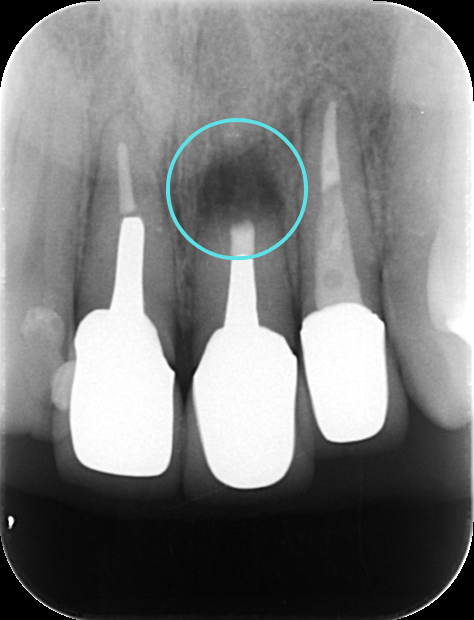

術後すぐ

術後3ヶ月のレントゲン写真

術後1年のレントゲン写真

根尖病変によって骨が溶かされてしまった空間も、歯根端切除術によって感染源が適切に除去され、根管が緊密に封鎖されると、体本来の治癒力によって再び新しい骨(新生骨)が作られていきます。 レントゲンでは、術直後は黒い影(骨がない状態)だった部分が、時間の経過とともに徐々に白く(骨が再生してきた状態)映るようになります。この「新生骨の出現」が、外科的歯内療法の成功を示す客観的な証拠となります。

今回の患者さんも、術後の定期検診にお越しいただきました。 術後6ヶ月の時点でのレントゲン写真では、手術前に黒い影として見えていた根尖病変部、および歯根を切除したスペースに、白く不透明な影、すなわち「新生骨」が順調に再生してきていることが明確に確認されました。